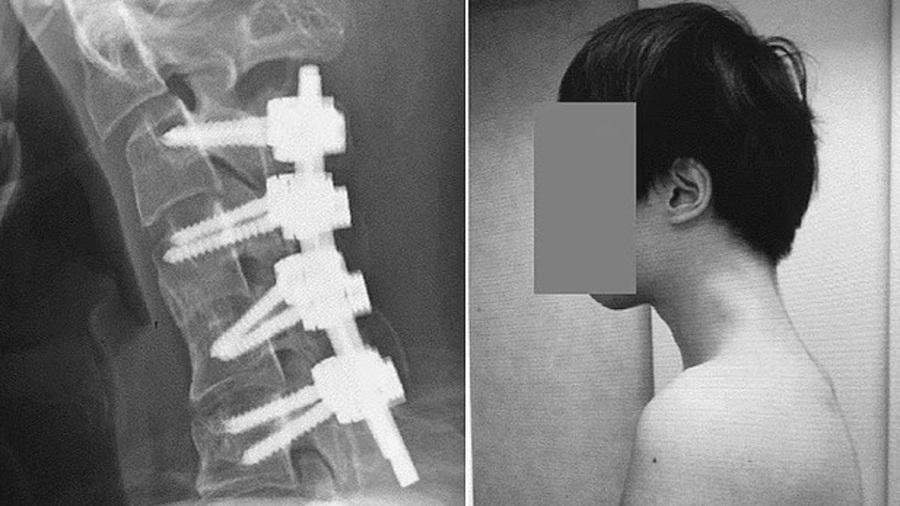

醫生初時嘗試用頸圈矯正該患者的頸椎,但因他戴上頸圈後感到麻痺,最後要做手術。醫生首先切除其小部分頸椎骨,以及頸部長出的疤痕組織,然後再安裝上螺絲和金屬桿承托其頭部並矯正彎曲的頸項。據悉,那名男子在手術後6個月,脊椎回復正常位置,他可容易抬頭至水平位置;後續1年跟進,他的抬頭和吞嚥問題也無再現。